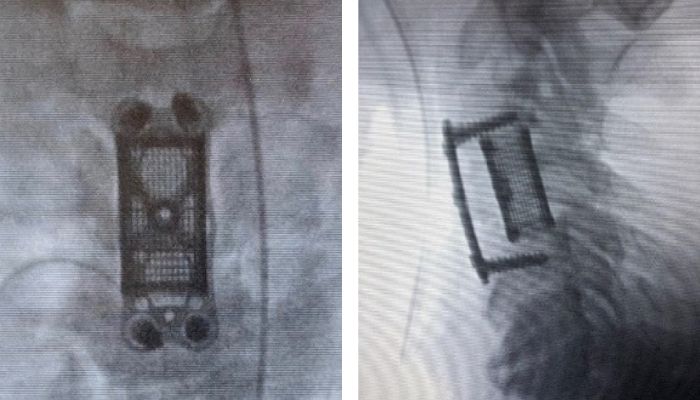

Nexxt Matrixx

The US company Nexxt Spine has been specializing in the manufacture of implants for spinal diseases for several years. With Nexxt Matrixx, the company has achieved another innovation: the 3D-printed titanium implants are intended to support osteogenesis, improve surface topography and promote the production of angiogenic factors. The naming seems to be inspired by the 75% porous grid of the implant, which promotes osteointegration and radiological visualization. The company uses equipment from GE Additive in the manufacture of its implants and thus relies on the DMLM process to manufacture its titanium parts. Andy Elsbury, the founder of Nexxt Spine states that patients and clinics particularly benefit from the strength and biocompatibility of the titanium implants.